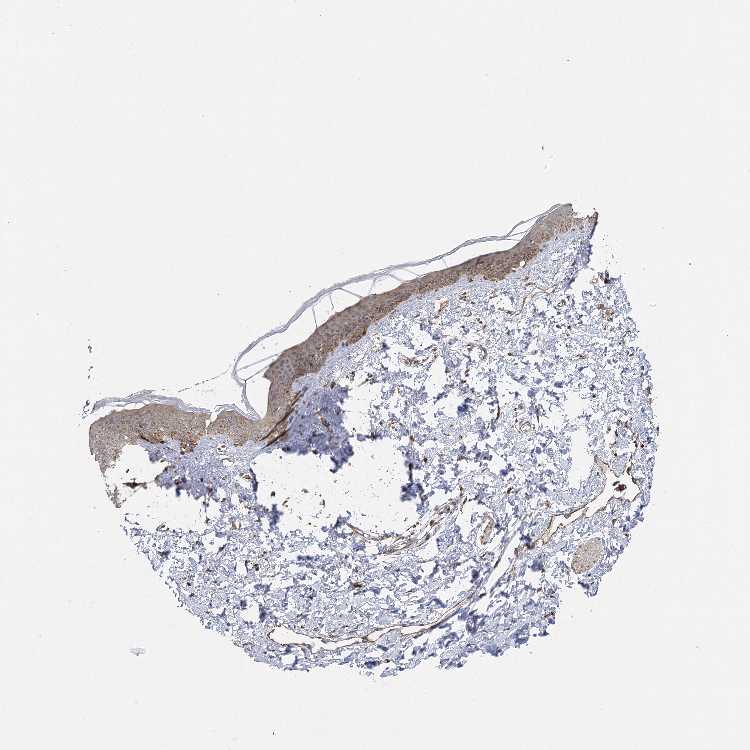

SKIN 2 - Antibody stainingi

Antibody staining in the annotated cell types in the current human tissue is reported as not detected, low, medium, or high, based on conventional immunohistochemistry profiling in selected tissues. This score is based on the combination of the staining intensity and fraction of stained cells.

Each image is clickable and will lead to virtual microscopy that enables deeper exploration of all samples and also displays staining intensity scores, fraction scores and subcellular localization as well as patient and tissue information for each sample.

Antibody HPA013162Antibody HPA036652Antibody CAB032830

Cells in basal layer -Medium-

Cells in corneal layer -Not detected-

Cells in granular layer -Medium-

Cells in spinous layer -Medium-

Endothelial cells -High-

Epidermal cells High-Medium

Extracellular matrix -Not detected-

Fibrohistiocytic cells -High-

Langerhans cells -Medium-

Lymphocytes -High-

Melanocytes -High-

Vascular mural cells -Not detected-